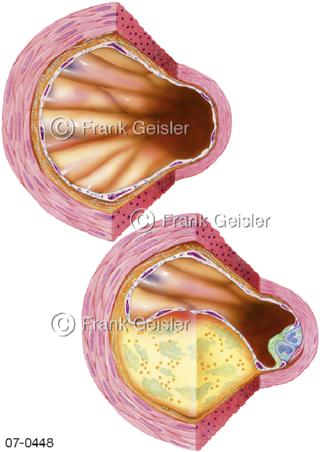

Bildergalerie Herz, Blutkreislauf

Bilder zu Herz, ein muskuläres Hohlorgan, das den menschlichen Körper durch rhythmische Kontraktionen mit Blut versorgt und dadurch die Durchblutung der Organe sichert, das Kreislaufsystem zeigt den Transport von arteriellem sowie venösem Blut durch das kardiovaskuläre System (Herz-Kreislauf-System), bestehend aus Blutgefäßen, Lymphgefäßen und dem Herz